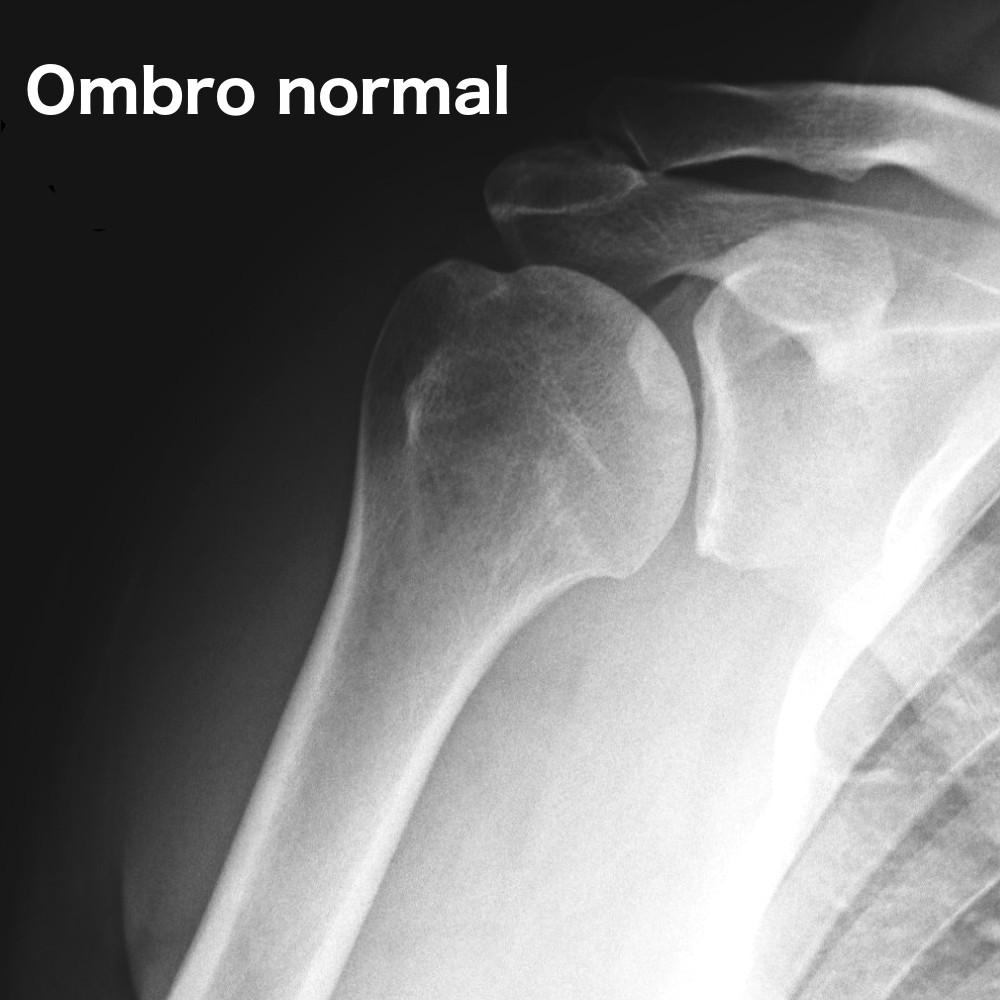

O diagnóstico dessa afecção é realizado através de uma história clínica e exame físico bem feitos. Uma radiografia simples geralmente é suficiente para confirmar o diagnóstico. A tomografia computadorizada pode ser solicitada para melhor avaliação do desgaste ósseo, para um planejamento terapêutico mais adequado. A ressonância magnética, embora não seja necessária para confirmar o diagnóstico, pode ser muito importante para avaliar a qualidade do manguito rotador. Essa avaliação, em muitos casos, também é essencial para se definir o melhor tratamento, principalmente na escolha do tipo de prótese que será usada caso esse seja o tratamento escolhido.